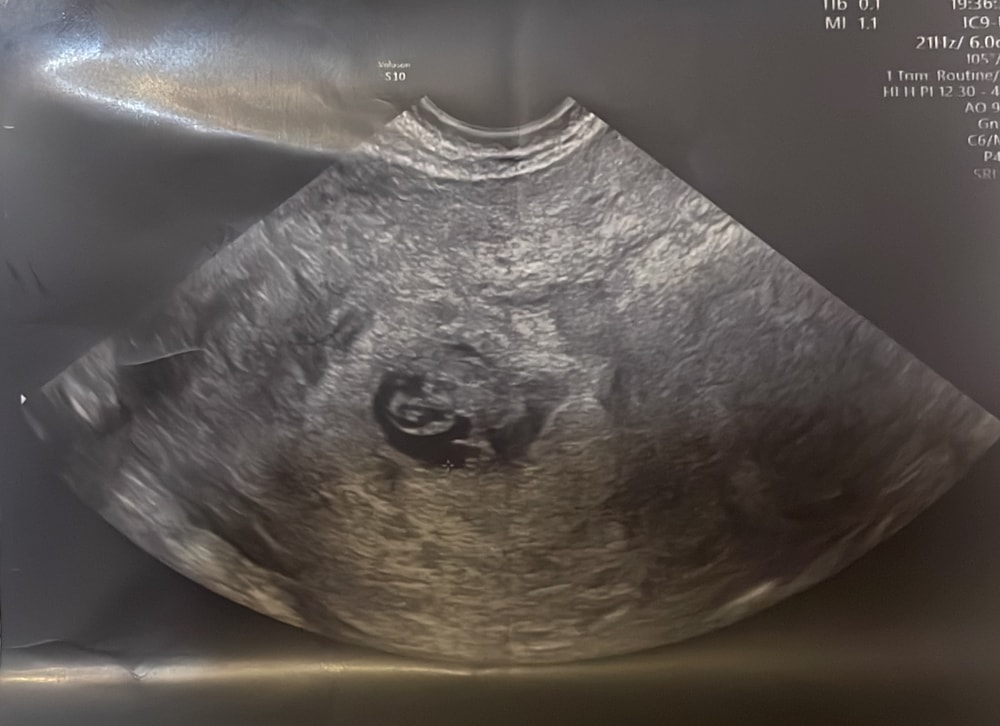

Еще фото такое дала , что будто там места то и нет 🤷🏻♀️😵💫и описания в емиас не прогрузилось . Хотя на той недели был даже с головой запас и даже с учетом , что мы подрасли не сильно , места все равно должно быть на эту неделю уж точно 🤔 оно было 26 мм ☹️ вообщем ее слова меня не подбодрили , а все наоборот расстроили . В тот раз тоже все началось с замедления роста пя ( теперь не знаю 🤷🏻♀️ идти прям сегодня переделывать , или дождаться неделю хотя бы и сделать

Spl♠, подождите немного и сделайте УЗИ в другом месте, последние время столько ошибочных замеров встречается, даже вот ваше фото,по нему нельзя определить,есть место или нет,так как смотря ещё с какого ракурса снимок сделать,это роль играет